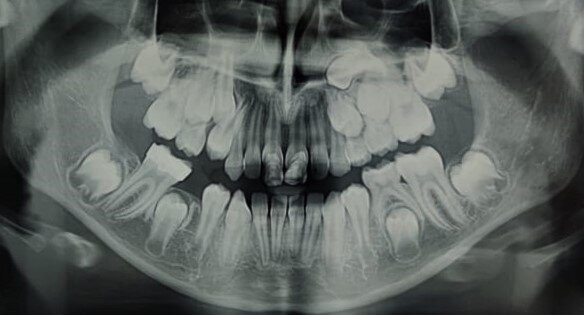

Eziologia La trasposizione dentale sembra avere una eziologia multifattoriale dove un ruolo importante è ricoperto dalle cause genetiche e dalle cause ambientali9. Alcuni Autori avvalorano maggiormente la teoria genetica10, sostenendo che un’alterazione nello sviluppo dentale produca, contestualmente alla trasposizione, varie anomalie dentali, quali ad esempio: agenesie dentali, incisivi laterali conoidi, etc. 2,7,11. Inoltre, l’interessamento bilaterale dello stesso dente, la presenza di trasposizione dentale in pazienti sindromici, come nella sindrome di Down12 o nella displasia cleidocranica13, il riscontro dell’anomalia in gemelli monozigoti14, sono altre evidenze che possono confermare l’eziologia genetica. In Figg. 1a, 1b è riportato un interessante caso di due gemelle eterozigoti che mostrano entrambe trasposizione canino-premolare mascellare e ritenzione canina.

Figg. 1a, 1b - Rx-OPT della paziente 1(A) e della paziente 2(B) gemelle di anni nove e mezzo entrambe in trattamento ortodontico intercettivo. Si nota la particolare e contemporanea presenza sia della trasposizione canina-premolare sia della ritenzione canina superiore.